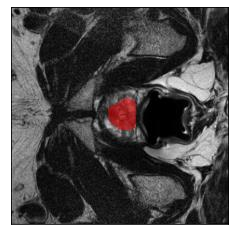

Machine learning models are typically deployed in a test setting that differs from the training setting, potentially leading to decreased model performance because of domain shift. If we could estimate the performance that a pre-trained model would achieve on data from a specific deployment setting, for example a certain clinic, we could judge whether the model could safely be deployed or if its performance degrades unacceptably on the specific data. Existing approaches estimate this based on the confidence of predictions made on unlabeled test data from the deployment's domain. We find existing methods struggle with data that present class imbalance, because the methods used to calibrate confidence do not account for bias induced by class imbalance, consequently failing to estimate class-wise accuracy. Here, we introduce class-wise calibration within the framework of performance estimation for imbalanced datasets. Specifically, we derive class-specific modifications of state-of-the-art confidence-based model evaluation methods including temperature scaling (TS), difference of confidences (DoC), and average thresholded confidence (ATC). We also extend the methods to estimate Dice similarity coefficient (DSC) in image segmentation. We conduct experiments on four tasks and find the proposed modifications consistently improve the estimation accuracy for imbalanced datasets. Our methods improve accuracy estimation by 18\% in classification under natural domain shifts, and double the estimation accuracy on segmentation tasks, when compared with prior methods.